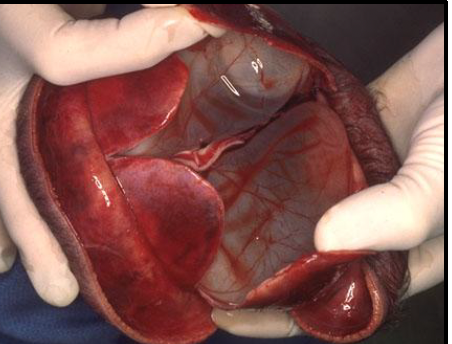

Letulle method almost always - important to preserve anatomic relationships

necrotizing enterocolitis (NEC) totalis

inflammation/infection of bowel causing tissue death, perforation, sepsis; commonly affects premature infants.